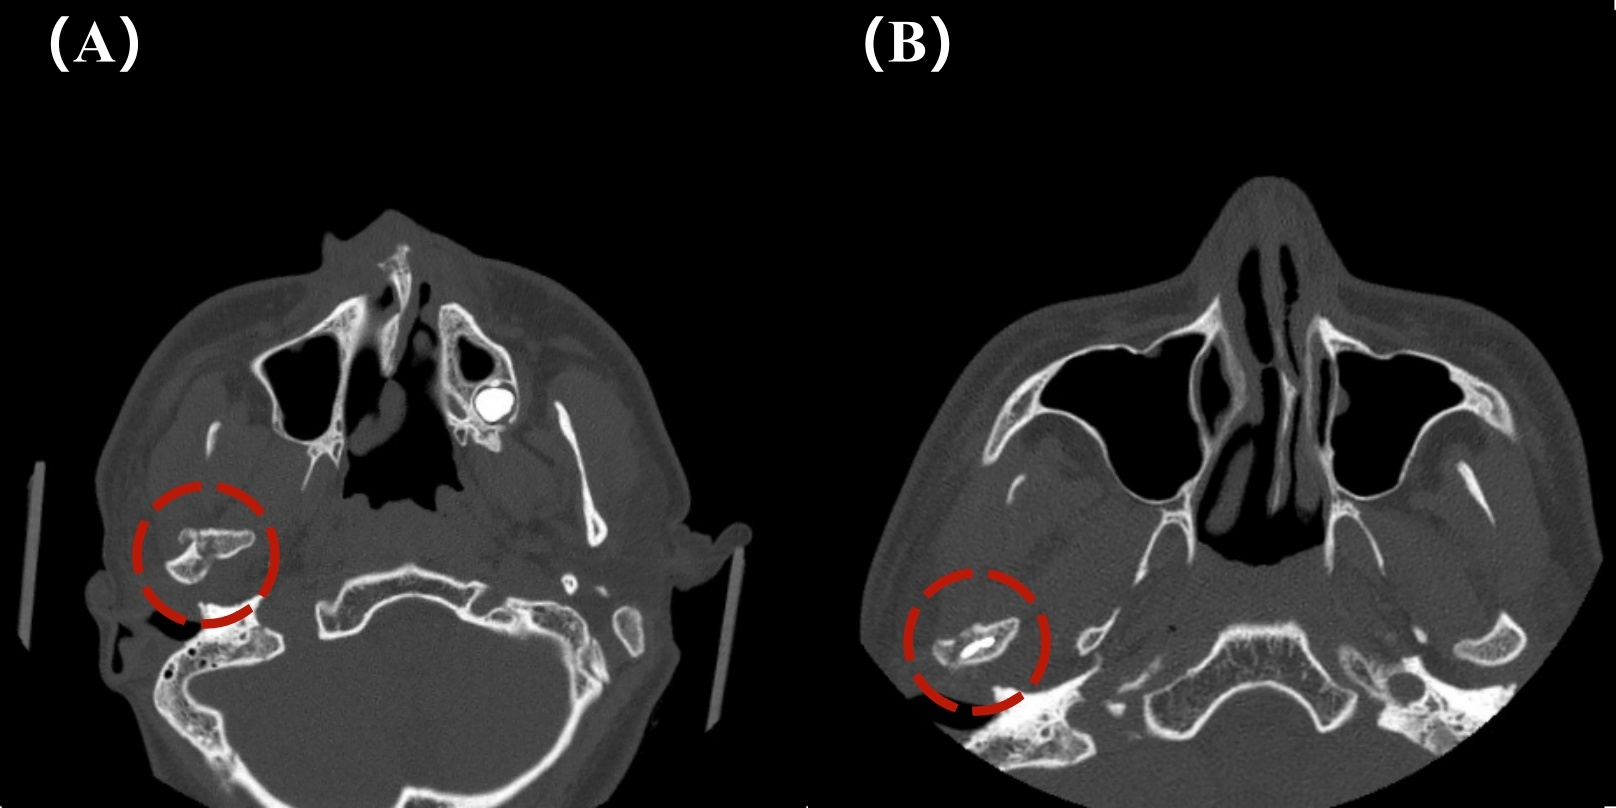

图3:颌面部CT三维重建水平位影像(A)术前;(B)术后

图4:颌面部CT平扫水平位影像(A)术前;(B)术后